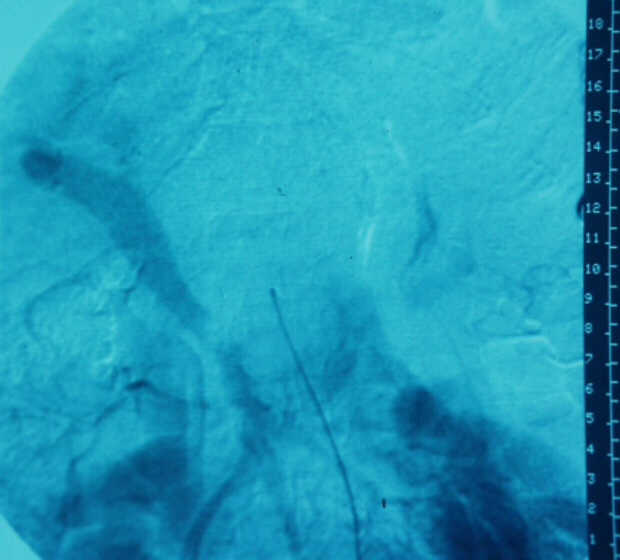

Diagnosis: Angiography

Giuseppe Morelli Coppola, Raffaella Niola, Franco Maglione

Unità Operativa di Radiologia Vascolare ed Interventistica, Azienda Ospedaliera "A. Cardarelli". Napoli, Italy